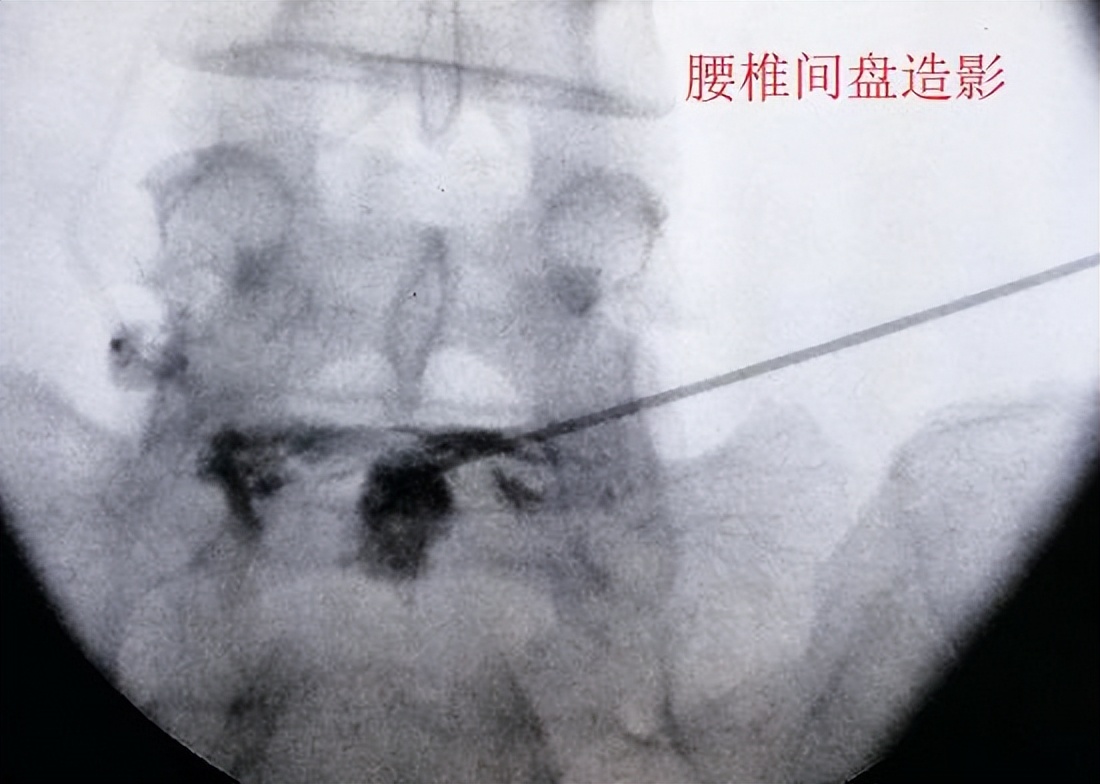

腰椎间盘突出可能会引发盘源性疼痛 腰椎间盘内部虽然没有神经组织,但神经组织却遍布椎间盘周围每一个角落(包括终板以外的软骨下骨),甚至还存在于椎间盘的外层纤维环。当腰椎间盘的退变和损伤程度足够严重时,外层纤维环的疼痛会被诱发,周边的神经和血管组织也会顺着微小裂隙向内生长,使神经组织深入到椎间盘内部,其后果便是引发盘源性疼痛(局限于椎间盘本身的疼痛)。在对这类疼痛进行治疗时,可采取局部封闭和阻滞的疗法(在此之前还应进行其他形式的保守治疗),一般不需要扩大治疗范围。

突出的髓核压迫神经根诱发下肢疼痛 向后外侧突出的椎间盘组织常常会压迫到神经根,这些神经根大概率是通往下肢的神经干,当其受到压迫时,并不会表现为压迫部位的疼痛,而是被压迫神经远端的组织疼痛(就如同一根通往主机房的网线在中途被老鼠咬坏,此时主机房只会检测到某台与这根网线相连的设备出了问题,并不知道是不是有一只老鼠正在咬网线)。解决此类疼痛最有效的方法是消除局部水肿,仅在必要时通过手术的方法进行解压。